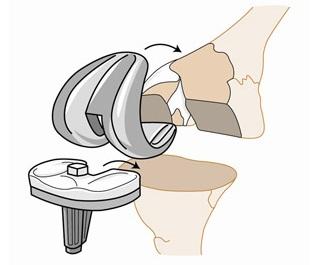

手术治疗包括关节清理术、关节融合术、关节置换术和关节镜等;